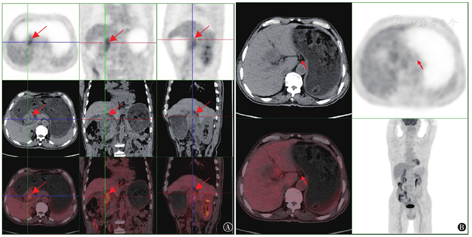

患者男,68岁,因上腹部不适于2020年8月24日就诊联勤保障部队第九八三医院,行电子胃镜检查:胃窦小弯可见巨大菜花样肿物,表面污秽。镜下诊断:胃癌;重度十二指肠炎。病理诊断:(胃窦)低分化腺癌伴印戒细胞癌成分。2020年8月26日于天津市肿瘤医院行胸、上腹平扫+增强CT(见图1A):胃体下部及胃窦胃壁不规则增厚,考虑胃癌,伴肝胃韧带区及胃窦周围多发淋巴结转移(较大者短径约1 cm)。肿瘤标志物检测结果(天津市肿瘤医院),CA242:208.0 U/ml,CA199:508.7 U/ml,CEA:3.73 ng/ml。2020年9月7日于天津市肿瘤医院会诊病理结果:(胃窦活检)低分化癌,首先考虑低分化腺癌。免疫组织化学:HER2(++),MLH1(+),PMS2(-),MSH2(+),MSH6(+),提示肿瘤可能为微卫星高度不稳定型(microsatellite instability-high,MSI-H)表型。原位杂交:EBER(-)。既往史:糖尿病病史6年余,应用精蛋白生物合成人胰岛素(预混30R)控制血糖,血糖控制尚可,存在糖尿病周围神经、血管、视网病变;冠心病病史7年余,长期口服硫酸氢氯吡格雷片(75 mg口服,1次/d)、单硝酸异山梨酯缓释片(40 mg口服,1次/d),病情稳定。家族史:父亲死于食管癌,哥哥死于肝癌,儿子死于胃癌。患者诊断明确,天津市肿瘤医院建议全身化疗后行手术治疗,家属商议后拒绝,自行口服中药治疗1月余(具体不详),效果不佳。

2020年10月13日因活动后胸闷气短就诊我院心内科,完善血常规提示血红蛋白76 g/L(为小细胞低色素性贫血)。胸部CT:双肺炎性病变伴间质性病变。颅脑MRI、放射性核素骨扫描、浅表淋巴结超声检查未见肿瘤转移性病变。2020年10月18日行程序性死亡蛋白配体-1(programmed death-ligand 1,PD-L1)检测:肿瘤细胞阳性比例分数(tumor proportion score,TPS)2%~3%,综合阳性评分(combined positive score,CPS)4。2020年10月22日基因检测提示:人体表皮生长因子受体-2(human epidermal growth factor receptor-2,HER-2)扩增阴性;高肿瘤突变负荷(tumor mutation burden-high,TMB-H);MSI-H。期间规律复查血红蛋白,血红蛋白进行性下降,2020年10月29日血红蛋白59 g/L。为进一步诊治转入肿瘤内科,查体:美国东部肿瘤协作组(ECOG)评分3~4分,神志清,精神差,重度贫血貌,卧床状态,浅表淋巴结未触及肿大,双肺呼吸音清晰,未闻及干湿性啰音;心律齐,未闻及病理性杂音;腹软,剑突下轻压痛,无反跳痛及肌紧张,肝脾未触及,腹部未触及包块,移动性浊音阴性,双下肢轻度凹陷性水肿。给予输注红细胞改善贫血及一般情况,病情好转后自2020年11月5日起给予替雷利珠单抗(200 mg/次,静脉滴注,1次/d,第1天,21 d为1周期,1年后改为每个月1周期)治疗。5个周期后评估疗效为部分缓解(partial response,PR)(见图1B),胃镜:胃窦溃疡并幽门梗阻。胃窦活检病理结果:黏膜慢性炎伴急性炎,纤维肉芽组织增生,溃疡形成,建议治疗后复查。治疗7、14、16个周期后评估疗效为维持PR。2021年11月15日于我院行PET-CT(见图2):胃腺癌治疗后,胃窦处胃壁明显增厚(胃窦胃壁最厚处27 mm),局部葡萄糖代谢增高(SUVmax3.9),考虑治疗后肿瘤组织仍有活性。自替雷利珠单抗治疗第1周期后患者血红蛋白均维持在90 g/L以上,肿瘤标志物进行性下降并维持在正常水平,治疗期间暂未发现药物相关不良反应,患者依从性良好。末次随访为2022年6月4日,患者精神、进食、睡眠尚可,大小便正常,无不适症状。